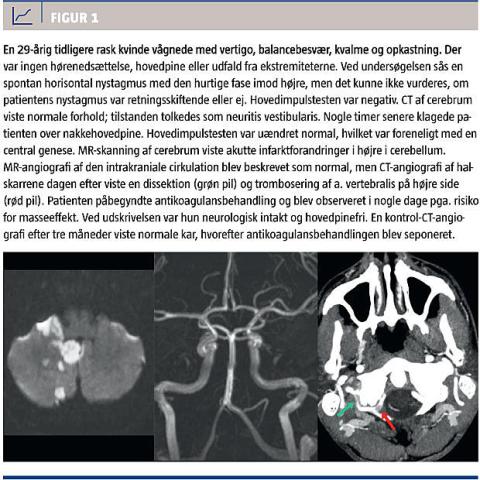

Centralt betinget vertigo kan skyldes iskæmisk eller hæmoragisk infarkt, tumor, infektion i centralnervesystemet eller en inflammatoriske tilstand (såsom et demyeliniserende plaque ved multipel sklerose). Den hyppigste årsag til akut central vertigo er iskæmiske infarkter i det bagre kredsløb, dvs. aa. vertebrales,

a. basilaris og dets forgreninger. Infarkterne opstår typisk på aterosklerotisk basis (f.eks. stenose/trombose i a. basilaris) eller på baggrund af tromboembolier, som kan være kardiale eller sekundære til

dissektioner af a. vertebralis. Specielt hos yngre patienter er den hyppigste årsag til infarkter i det bagre kredsløb en a. vertebralis-dissektion [4-6] (Figur 1). De fleste cerebellare infarkter har en god langtidsprognose, men i 10-25% af tilfældene vil der tilstødte masseeffekt med risiko for hjernestammekompression, hydrocefalus, kardiorespiratoriske komplikationer, koma og død [7, 8].

hyppigt inden for de første 24 timer, hvorfor billeddiagnostikken bør gentages efter 48 timer [4]. Ved infarkter i det bagre kredsløb anbefales altid apopleksiudredning i hht. gældende vejledninger og anbefalinger, hvilket som regel inkluderer MR-skanning eller CT-angiografi mhp. fremstilling af de intra- og ekstrakranielle kar inklusive aortabuen (dette er

vigtigt for at afsløre basilaristromboser og vertebralisdissektioner (Figur 1)) og udredning for kardiale

embolikilder.